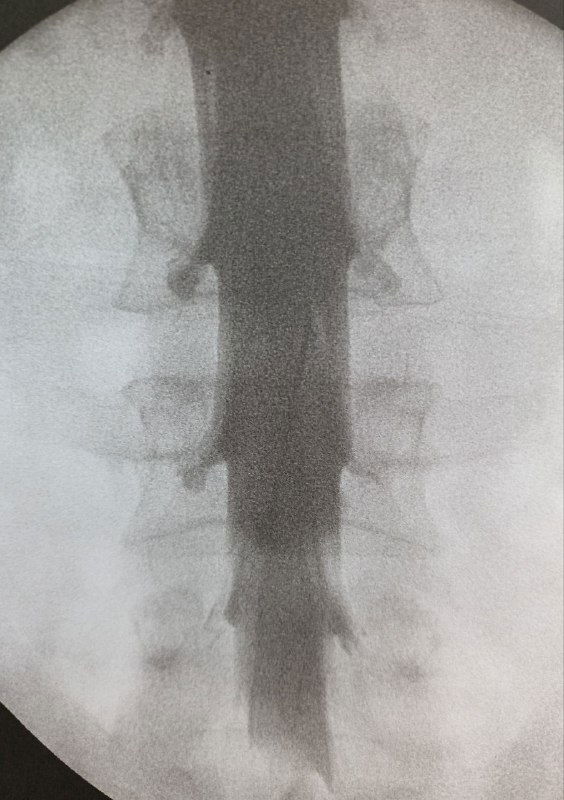

Краткая заметка о вертебропластике: простая и эффективная процедура, требующая планирования угла иглы и скорости введения костного цемента.